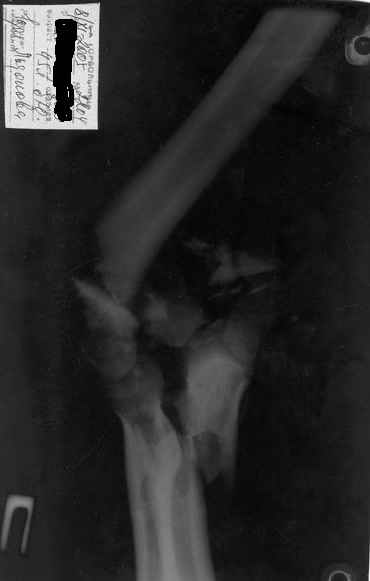

Здравствуйте, коллеги.Мужчина, 45 лет, ДТП 24.10.05. На сегодня неврологических расстройств правой кисти нет, отека нет, движения в правом плечевом и в правой кисти в полном объеме. Правый локтевой сустав сгибани 110*, разгибание 140*, наружняя ротация предплечья 45*, внутренняя 45*. Укорочение правого плеча 4 см. Больной просит у меня совет, стоит ли ему стремиться к эдопротезированию локтевого сустава.Я, к сожелению, не видел ни одного больного после эндопротезирования локтевого сустава.-- С уважением,Анатолий Борзунов

Имея небольшой опыт эндопротезирования локтевого сустава (3 операции - 2 эндопротеза типа Сиваша, и 1 - RM), считаю, что основным показанием к эндопротезированию этого капризного сустава является его гипермобильность (в результате перелома с формрованием разболтанного ложного сустава см. форум от 06.04 2006), или выраженный болевой синдром в сочетании с тугоподвижностью (что встречается у наших больных с гемофилической артропатией). Собственные результаты в целом неплохие - отсутствие болей и гипермобильности, однако, имеется некоторое ограничение разгибания. Сама

операция сопровождается мобилизацией локтевого нерва, а в условиях нарушенной анатомии сросшегося оскольчатого перелома имеется высокая вероятность его травматизации во время выделения, с вытекающими проблемами.